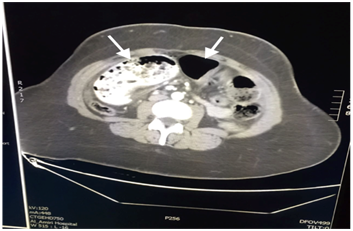

A 25-year-old woman presented with a history of controlled hypothyroidism, Laparoscopic Sleeve Gastrostomy (LSG) in 2012, and a combined Roux-en-Y gastric bypass and cholecystectomy in 2015. She presented to one of our regional hospital surgical facilities in 2016 with a 1-day history of diffuse, non-radiating, constant, and colicky abdominal pain associated with anorexia and constipation. On examination, she was vitally stable, her abdomen was grossly distended and severely tender with evidence of guarding, and her bowel sounds were absent on auscultation. Subsequently, a Computed Tomography (CT) scan of the abdomen was done, revealing a hiatal hernia of the bypassed stomach pouch with evidence of dilated jejunal and proximal ileal loops reaching 5 cm in diameter (Figure 1), and free extraluminal air locules were seen in the right side of the upper abdomen and perihepatic region (Figure 2), along with mild free intra-abdominal free fluid and diffuse fat stranding (Figure 3). She was admitted as a case of acute abdomen and small bowel obstruction secondary to bowel perforation; she was immediately booked for diagnostic laparoscopy.

Figure 1 CT scan of the abdomen revealing a hiatal hernia of the bypassed stomach pouch with evidence of dilated jejunal and proximal ileal loops reaching 5 cm in diameter (arrows).